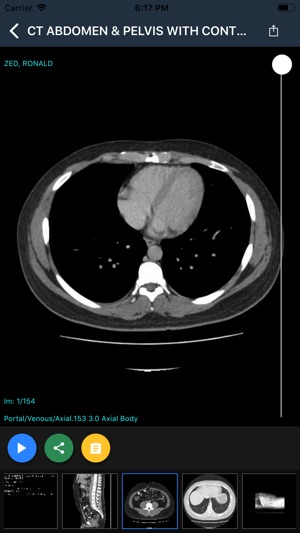

Zed Doctor is an app for viewing medical imaging studies. Please contact us at support@zedtechnologies.com.au for your free account.

The viewer displays selected studies and reports via an intuitive user interface and allows key images and associated reports to be forwarded to other referrers involved in patient management.